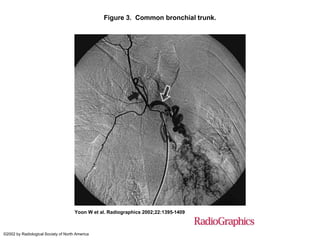

Figure 3. Common bronchial trunk.

Yoon W et al. Radiographics 2002;22:1395-1409

©2002 by Radiological Society of North America

Figure 3. Commonbronchial trunk. Yoon W et al. Radiographics 2002;22:1395-1409 ©2002 by Radiological Society of North America

• #73 Figure 3.  Common bronchial trunk. On a selective bronchial angiogram, the right intercostobronchial artery (black arrow) and a pathologic left bronchial artery (white arrow) are seen to arise from a common trunk and supply hypervascular lesions in the left lower lobe.